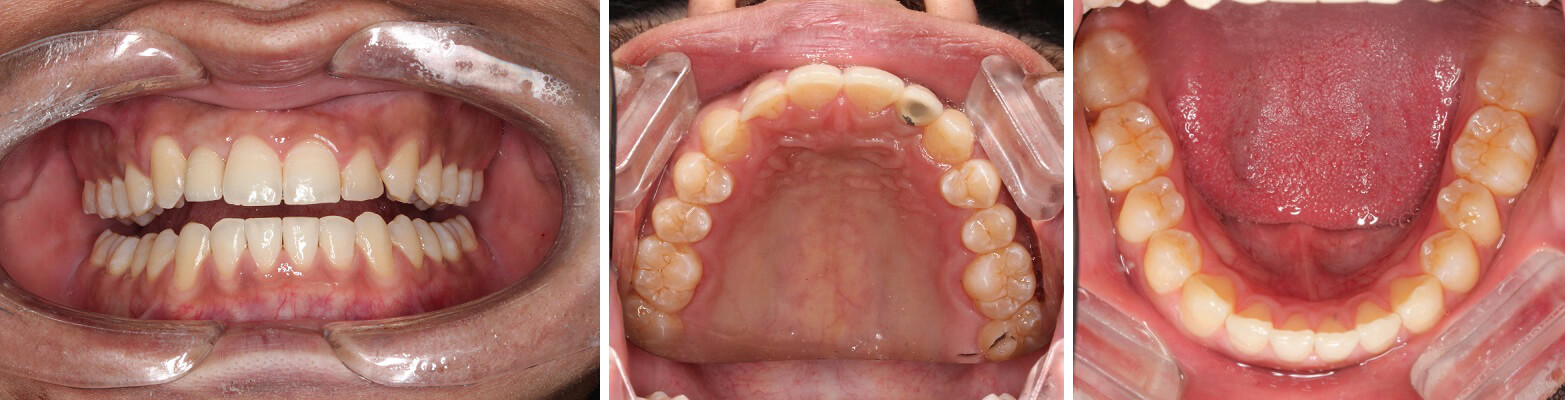

Deep bite has been corrected with braces and teeth have been aligned to perfect arch and no teeth extraction required.